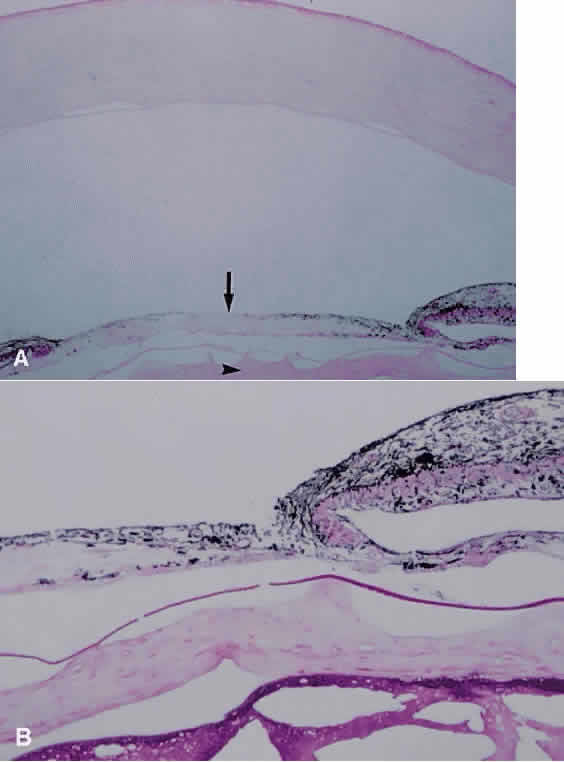

Acute nongranulomatous uveitis typically does not result in the need for enucleation or even biopsy; therefore, histopathologic examination of human eyes in the acute stages of the disease is rare. When enucleation is needed, it usually is at the end stage of the disease, when all attempts to preserve vision or comfort or both have failed. Thus, most histopathologic descriptions of human uveitis are from chronically inflamed eyes and show mostly an infiltration with chronic inflammatory cells (Fig. 2). Most of the information regarding events in acute uveitis has been gained from the use of various animal models of uveitis. Several models exist, but all are based on a similar principle: that of bypassing the normally existing state of self-tolerance and stimulating an organism to attack its own ocular tissues. This is accomplished by the subcutaneous inoculation of various substances (including retinal S antigen, interphotoreceptor retinoid-binding protein [IRBP], and melanin-associated proteins) into laboratory animals. A variable period later, depending on the specific model, uveitis develops, which can then be studied. In experimental autoimmune anterior uveitis, inoculation of Lewis rats with melanin-associated proteins produces primarily anterior segment disease,17–20 with minimal retinal involvement. Perhaps the most widely studied animal model of endogenous posterior uveitis is experimental autoimmune uveoretinitis (EAU), induced by the inoculation of either the retinal S antigen or IRBP into susceptible strains of animals. Other models of uveitis include bacterial product-induced intraocular inflammation. In endotoxin-induced uveitis, injection of bacterial endotoxins directly into the vitreous cavity or systemically produces inflammation localized primarily to the anterior segment in Lewis rats.21

Fig. 2. A. Photomicrograph of iris root and anterior chamber angle. There is apposition of iris to trabecular meshwork with closure of the angle by peripheral anterior synechiae (arrows) (hematoxylin and eosin; × 200). B. Chronic inflammatory cells including plasma cells (arrow) and lymphocytes (arrowhead) can be seen within the iris stroma (hematoxylin and eosin; × 500).

Early events in EAU include expression of adhesion molecules on the surface of retinal vascular endothelium, allowing the adherence of circulating leukocytes and subsequent infiltration into the retina.22,23 In Lewis rats, the acute cellular infiltrate is composed of neutrophils and primarily affects the retina (Fig. 3) and anterior segment.24 CD4+ T cells have been found necessary for the development of EAU25 and are stimulated by presentation of antigen in the setting of MHC class II-expressing cells.26 There is likely a genetic susceptibility to the development of EAU,27 which may help explain occurrence of uveitis in only certain individuals. Once initiated, much of the damage resulting from EAU, and most likely in human uveitis, is caused by the production of numerous oxygen-derived radicals (e.g., superoxide, hydrogen peroxide, hydroxyl radicals, peroxynitrite), which directly attack the photoreceptor layer, producing oxidative damage to these sensitive light-sensing cells.28–30

Fig. 3. Photomicrograph of retina of Lewis rat 13 days after injection of S antigen in complete Freund's adjuvant to hind footpad. Inflammatory cell infiltrate exists within the retina as well as in the subretinal space. Photoreceptor layer is destroyed (hematoxylin and eosin; × 200).